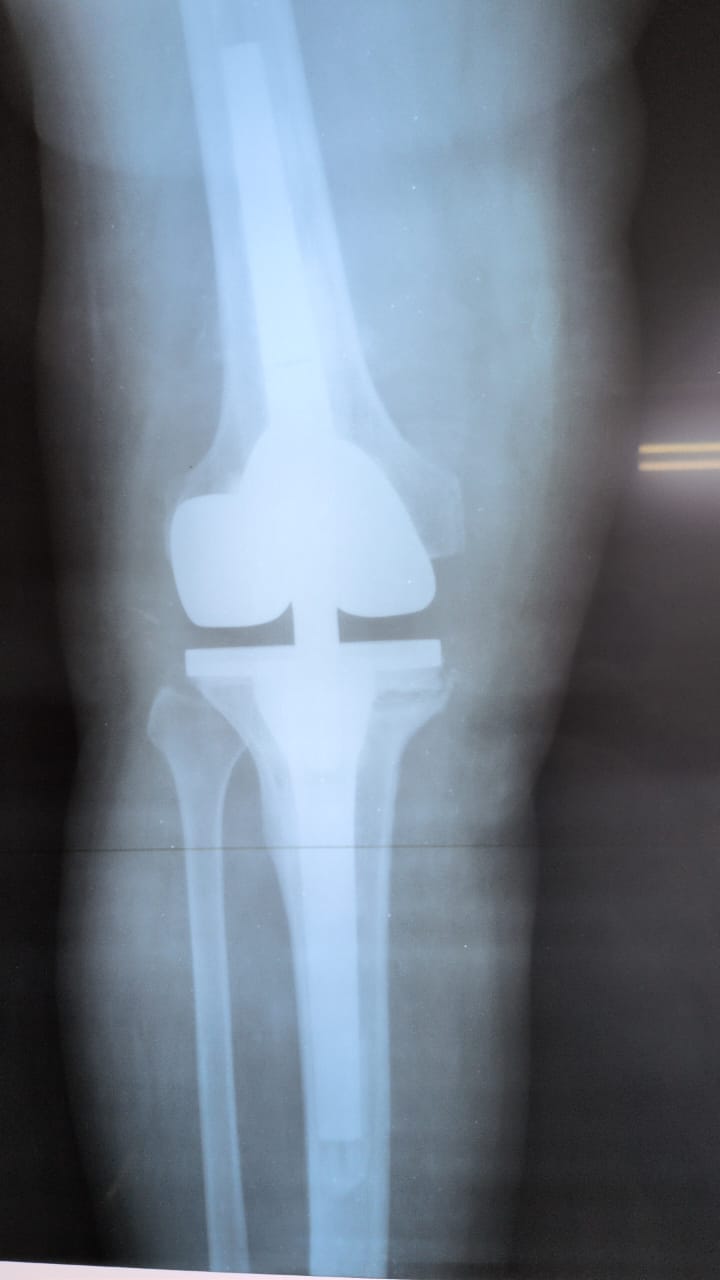

Galerie d’implants & imagerie

Exemples pédagogiques de prothèses et d’ostéosynthèses pratiquées à la CCL.

PTG — face